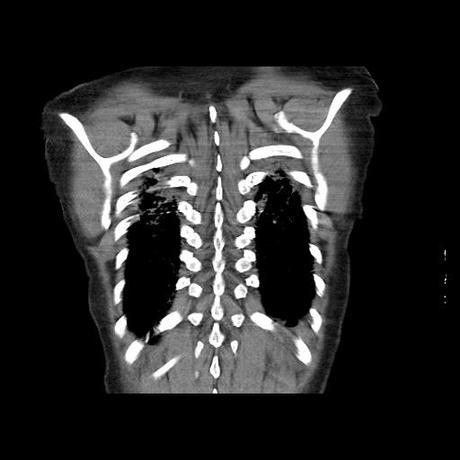

Se realiza volumen de tórax en fase simple, desde los opérculos torácicos hasta los hemidiafragmas, observándose:

El parénquima pulmonar con areas parcheadas difusas en vidrio despulido combinadas con otras areas hipodensas de baja atenuación debidas a atrapamiento aéreo y engrosamiento intersticial y zonas de fibrosis de predominio en lóbulos medios e inferiores de ambos pulmones.

- LOS HALLAZGOS PUEDEN ESTAR EN RELACIÓN A NEUMOPATIA INTERSTICIAL PROBABLE ETIOLOGIA HIPERSENSITIVA VS AUTOINMUNE/BACTERIANA/FUNGICA.